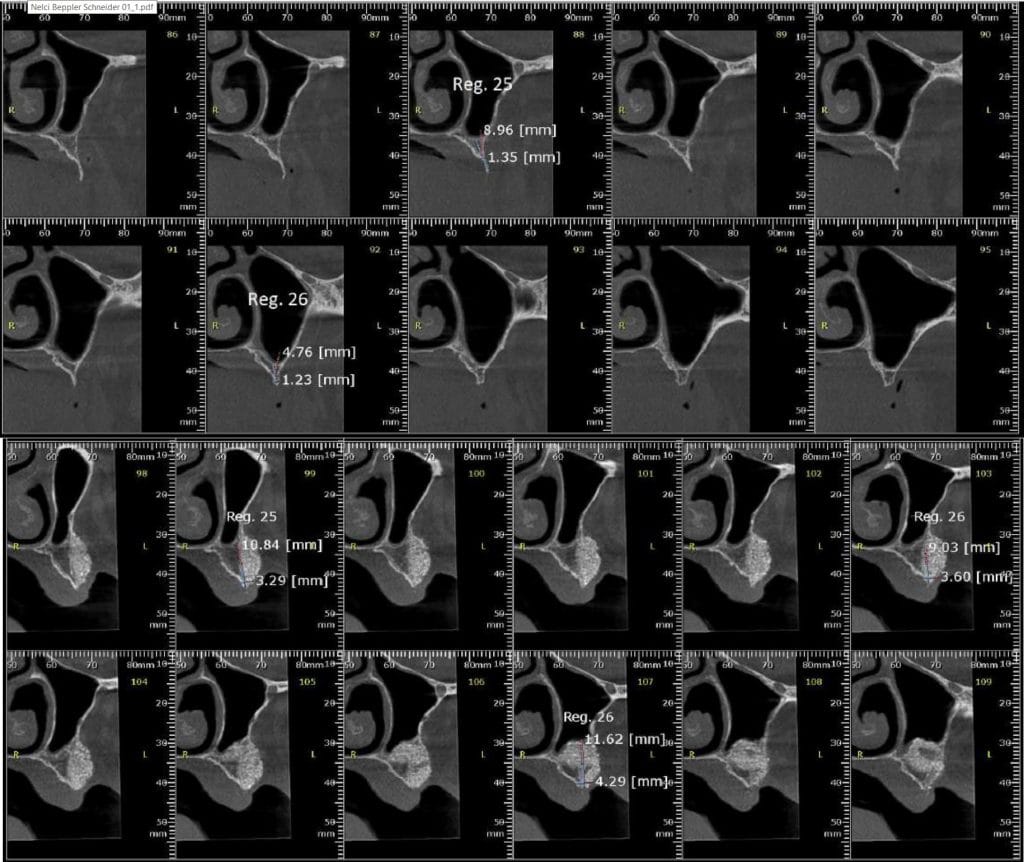

Olá colegas, aqui está um caso didático de reconstrução óssea total da maxila, levantamento do seio maxilar bilateral e bloqueio espesso com aplicação do conceito de PRF e Biotensigrity.

SEM tela, SEM parafusos, SEM membranas de colágeno. Substitua apenas osso aloplástico e sangue.

Após 6 meses de maturação óssea e implantes instalados com torque médio de 35 N / cm2.